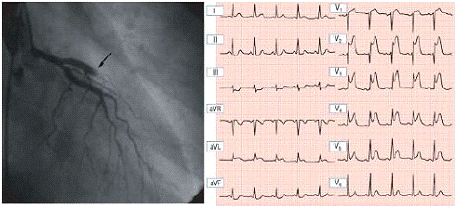

Рис. 1. Нижний острый ИМ: окклюдированная правая венечная артерия, подъем сегмента ST в отведениях II, III и aVF; ST угнетение от V1 до V4.

Рис. 2. Передний острый ИМ: окклюдированная левая передняя нисходящая венечная артерия, подъем сегмента ST.